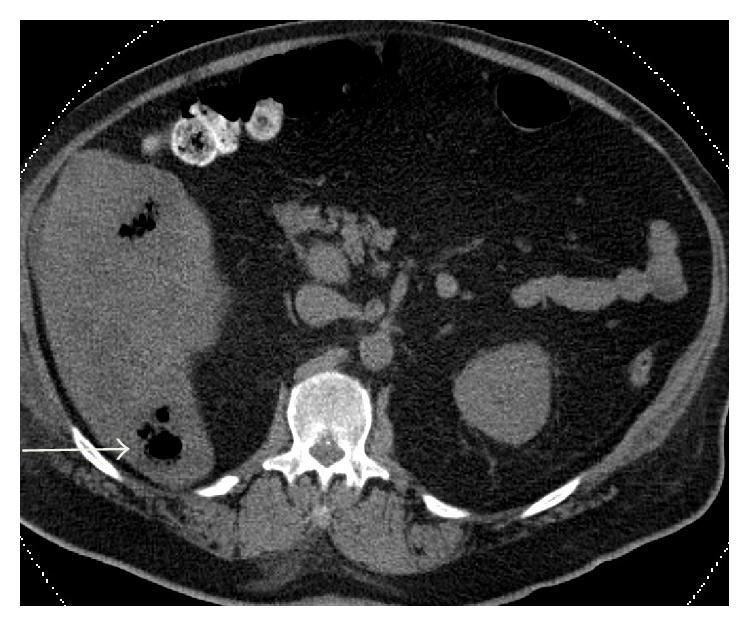

梭菌属细菌可引发一些最为致命的疾病,包括气性坏疽、破伤风和肉毒中毒。败血梭菌是一种罕见的亚群,已知可导致非创伤性肌坏死,且与结肠恶性肿瘤或免疫抑制有关。它是一种革兰氏阳性、厌氧、产芽孢杆菌,存在于胃肠道中,可导致肠道和腹膜腔的直接、自发性感染。肿瘤的无氧糖酵解产生酸性、缺氧环境,有利于梭菌芽孢的萌发。肿瘤引起的黏膜溃疡使芽孢化细菌从肠道转移到血液中,导致暴发性败血症。败血梭菌菌血症的表现可能各异,死亡率超过60%。如果不及时开始诊断和采取适当的治疗措施,大多数死亡发生在最初24小时内。我们报告一例新诊断为结肠癌患者发生腹部肌坏死的病例。本研究的目的是强调对患有潜在结肠恶性肿瘤的患者保持高度怀疑败血梭菌感染的重要性。